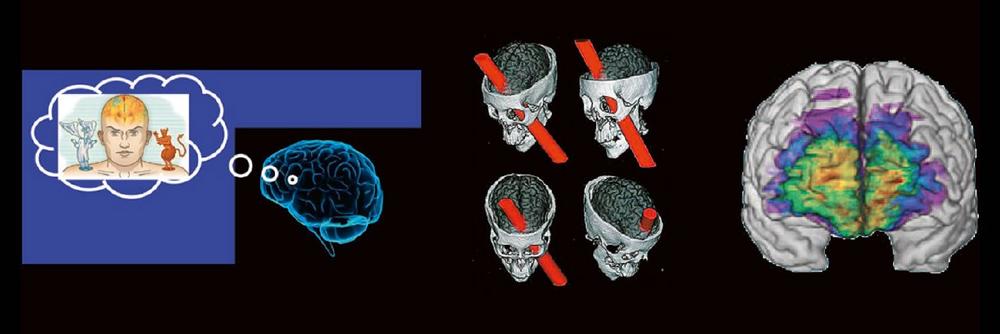

Das Treffen moralischer Entscheidungen erfordert – wie jede andere Hirnleistung auch – das Zusammenwirken verschiedener Hirnareale. Der Vortrag nimmt auf eine interaktive Reise durch die Mehrzügeligkeit moralischer Entscheidungen (emotional vs. utilitaristisch) und gängiger moralischer Dilemmata (Trolley-Problem) und führt schließlich zu den mit dem Treffen dieser Entscheidungen befassten Hirnregionen und zu den Auswirkungen auf moralische Entscheidungen bei Schädigung dieser Hirnareale.